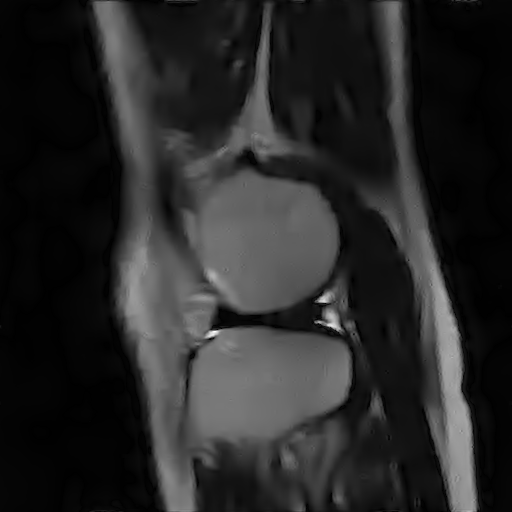

V-C Denoising of a magnitude MR knee image

We have also applied our CURE-LET denoising algorithms to an actual magnitude MR image of the knee. This 16-bit raw image has been acquired on a Siemens 1.5 Tesla Magnetom Sonata MR system, following a sagittal T2-weighted protocol. The standard deviation of the complex Gaussian noise has been estimated from a signal-free region of the squared data, as , and subsequently treated as known.

Fig. 11 shows the denoising results of the various CURE-LET algorithms. As observed, the noise is efficiently attenuated and the contrast is significantly improved, owing to a proper reduction of the signal-dependent bias introduced by the noise.